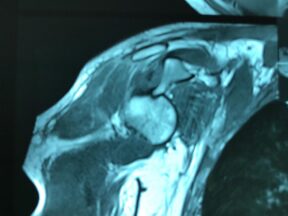

Angioresonancia periférica (miembro superior derecho).

Pacientes con luzación glehumeral anterior y fractura diafisiaria del humero, de un mes de evolución. Se complica con una oclusión de un segmento de la arteria subclavia-axilar, secundaria a trombosis.

Las lesiones de vasculares asociadas a fracturas y luxaciones del hombro son poco frecuentes, aunque potencialmente muy graves por lo que requieren un diagnóstico y actuación urgentes. Debido a la proximidad anatómica, pueden coexistir signos de compromiso de nervios mediano, radial y cubital.